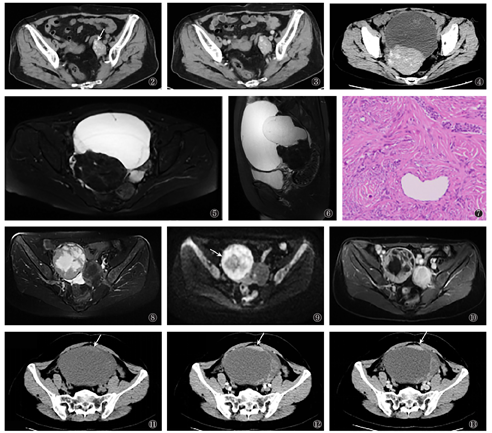

1个良性病灶行CT平扫检查,16个行CT平扫+增强检查。13个呈完全实性,4个呈囊实性。17个病灶实性成分于CT平扫均呈等、稍高密度,平扫CT值40.8~ 77.0 HU,平均CT值(56.6±12.7)HU。12个(70.5%)病灶实性成分内可见多发无定形钙化(图2)。增强CT扫描显示1个病灶实性成分呈明显强化,15个病灶实性成分呈轻度强化(图3),CT值强化幅度为7.9~ 39.8 HU,均值(17.3±9.0)HU。4个囊实性病灶的囊性成分均呈偏侧性、外生型(图4)。

本研究中,2例交界性Brenner瘤均行MR平扫及增强;1例恶性Brenner瘤行CT平扫及增强。这3例均为单侧病灶,且均呈囊实性,囊变呈中央型,囊内分隔厚薄不均,肿瘤实质均位于病灶边缘,呈不规则状、结节状。2个交界性病变平均直径分别为7.3 cm、12.4 cm,肿瘤实质T2WI及DWI均呈稍高信号,增强扫描均呈中度强化(图8,图9,图10)。1个恶性病变平均直径为13.2 cm,肿瘤实质CT平扫呈等密度,增强扫描呈明显强化,强化幅度为49.8 HU(图11,图12,图13)。这3例病灶均未见钙化。

典型的良性Brenner瘤影像多表现为单侧、完全、实性肿块[6],肿块实质部分有丰富的纤维组织,T2WI通常呈等低信号,CT平扫呈稍高密度,增强后多呈轻度延迟强化[6],本组12个病灶呈多发无定形钙化,与研究结果钙化情况可作为诊断Brenner瘤的重要征象相符[6]。目前,有关良性Brenner瘤呈囊实性肿块的研究较少[6,7]。良性囊实性Brenner瘤的实质密度、信号与典型Brenner瘤类似,区别在于前者实性部分多位于病灶边缘、偏侧性,其囊性结构可呈单囊、多囊;本研究中,9个囊实性病灶囊性部分均呈外生型生长,提示外生型囊性病变可能是良性Brenner瘤的典型征象。交界性及恶性Brenner瘤病灶多较良性病变体积大,以囊实性多见。本组2例交界性及1例恶性Brenner瘤均呈囊实性,且囊变多位于病灶中央,这可能与肿瘤生长速度较快,病灶体积较大,中心液化坏死形成有关;其实性成分明显强化,可能与肿瘤恶性程度增加,肿瘤血供随之增加有关。

囊实性Brenner瘤的鉴别诊断:(1)纤维卵泡膜细胞瘤:该病多表现为囊实性,通常囊变位于病灶内,呈大片状、不规则状[9](图14),良性囊实性Brenner瘤囊变多为外生型(图15);但前者与中央囊变坏死的交界性及恶性Brenner瘤鉴别困难。且前者肿瘤实性部分与Brenner瘤表现相似,易被误诊。(2)囊腺肿瘤:该病为卵巢常见肿瘤,可发生于附件区。卵巢囊腺瘤多呈囊实性,囊变可呈单房或多房,囊内分隔随肿瘤恶性程度增加可厚薄不均,囊腺瘤或囊腺癌实性成分多呈结节状附于囊内壁,即壁结节,囊变呈多房状,内分隔厚薄不均匀(图16),实质区域T2WI呈稍高信号,增强后可见明显强化,恶变时多伴大量腹水、腹膜腔内网膜广泛种植性转移等[9];Brenner瘤较少出现上述征象。(3)颗粒细胞瘤:本病多呈囊实性,内部多发囊变,且伴雌激素升高,实质区域T2WI信号稍高,增强后呈中度至明显强化,囊变多呈"蜂窝状"征象(图17)[10]。